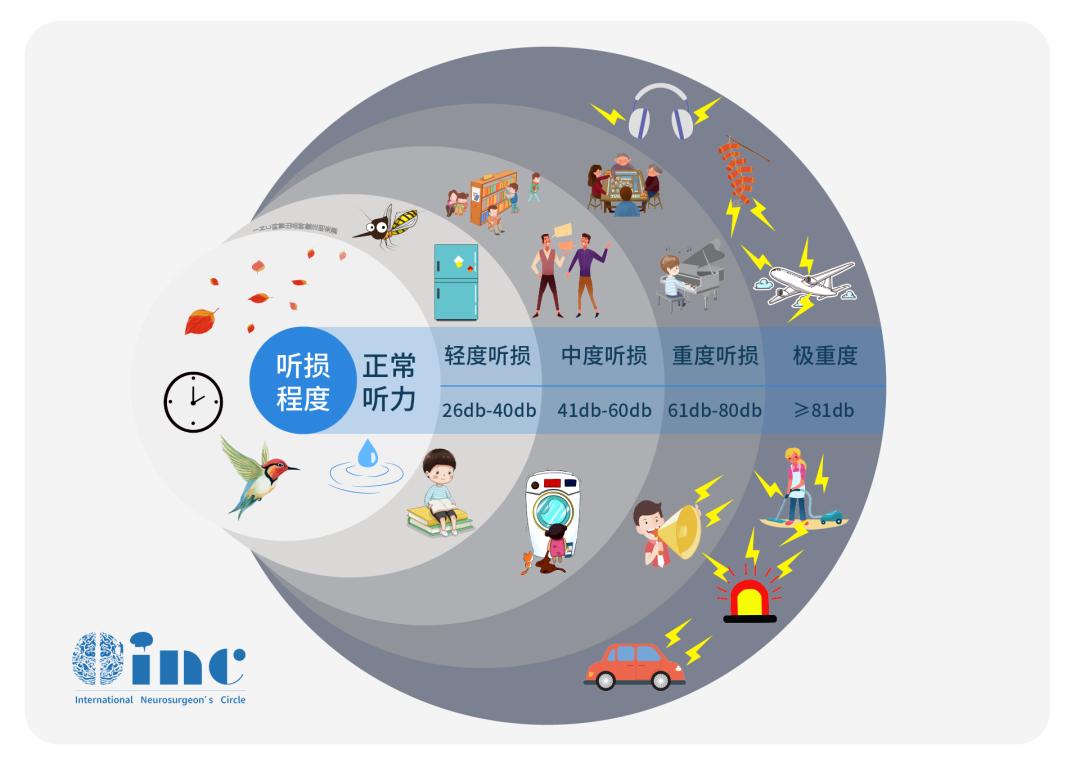

下丘脑不仅通过神经和血管途径调节脑垂体前、后叶激素的分泌和释放,而且还参与调节自主神经系统,如控制水盐代谢、调节体温、摄食、睡眠、生殖、内脏活动以及情绪等。...